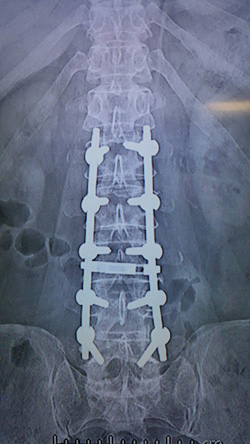

Nörolojik bulgunun varlığı cerrahi nedendir. Sadece ağrı ve/veya kladikasyo tanımlayan hastalarda 3 - 6 haftalık konservatif tedavilere cevap alınamaması da cerrahi neden olarak kabul edilir. Cerrahi yöntemlerin genel prensibi kanal çapının genişletilmesidir. Bu genişletme cerrahileri sonrası hastanın bacak ağrıları geçer. Yürüme mesafesi normale döner. Kanal çapının eski haline döndürülmesi mikrocerrahi yöntemlerle yapılır. Hastalarda ayrıca omurga bozuklukları, kaymaları ve eğilmeleri (skolyoz) varsa bu hastalara titanyum plak vidalar uygulanarak omurga şekli düzeltilir. Hasta daha dik bir hale gelir.